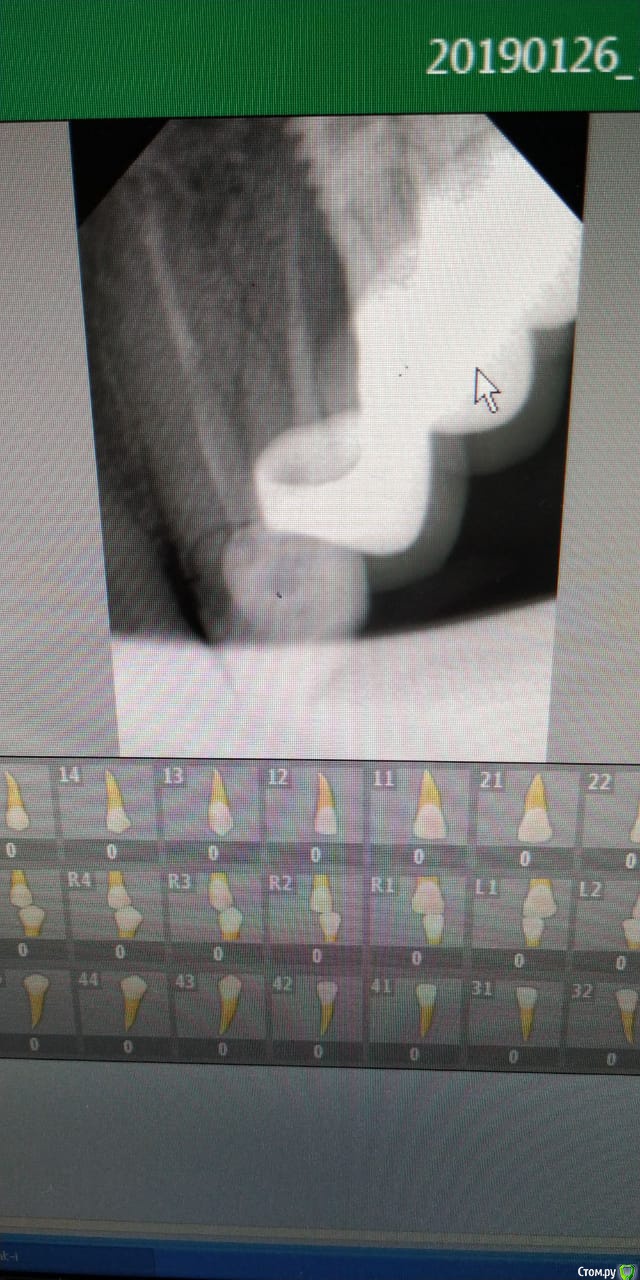

Kreveta Опубликовано 25 января, 2019 Автор Поделиться Опубликовано 25 января, 2019 Сделала ещё один снимок - перелом корня зуба, так что всё очень плохо((( Ссылка на комментарий

Kreveta Опубликовано 27 января, 2019 Автор Поделиться Опубликовано 27 января, 2019 (изменено) покажите? Изменено 27 января, 2019 пользователем Kreveta Ссылка на комментарий

Kreveta Опубликовано 27 января, 2019 Автор Поделиться Опубликовано 27 января, 2019 (изменено) Уже поставила имплант + временную коронку Изменено 27 января, 2019 пользователем Kreveta Ссылка на комментарий